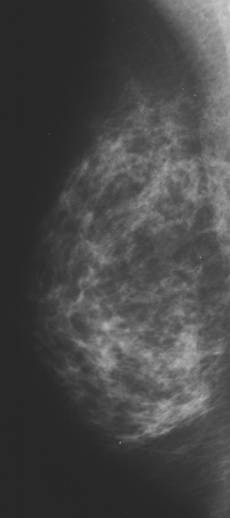

Mammograms from the National Health Service Breast Screening Programme were used as a baseline measure, with follow-up imaging done a year later. Warren and Sala assigned Wolfe patterns, and visually estimated the percentage density of each set of mammograms.

| Women taking an isoflavone tablet daily for one year showed a changeover to a more lucent Wolfe pattern on mammography. The differences between the treatment group and the placebo group were not statistically significant (p = 0.31). All images courtesy of Dr. Ruth M.L. Warren. |

The results showed there was no difference in estimated percentage density at baseline, mean of 61.8% according to Warren and 61.6% based on Sala's read, or follow-up (58% and 57.4%, respectively). Mammographic density did decrease in both groups, but the difference between treatment and placebo was not statistically significant, the authors wrote.

According to Warren's read, 22% of the women in the isoflavone group changed to a more lucent Wolfe pattern versus 18% of the placebo group. There was no change for 78% and 80%, respectively, and only a 2% change to a denser Wolfe pattern in the placebo group.

According to Sala's read, 15% of those taking isoflavones exhibited a more lucent Wolfe pattern compared to 19% in the placebo group. Eighty-four percent of the women on isoflavones showed no change, as did 80% of the women taking the placebo. Finally, only 2% of both groups showed a denser Wolfe pattern.